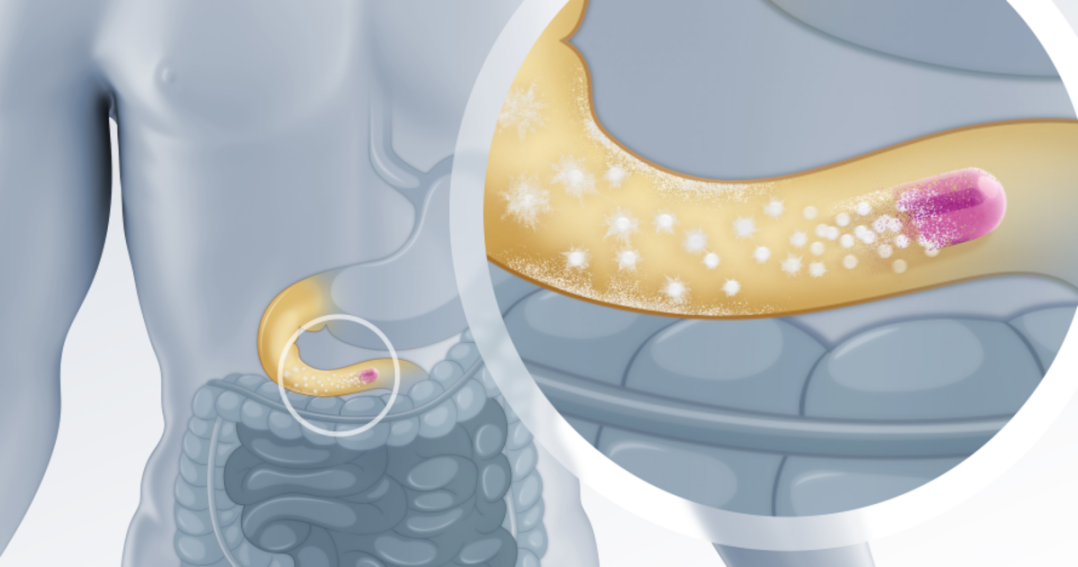

एंटरिक-लेपित गोलियों के लिए विघटन अध्ययन में प्रगति

एंटरिक-लेपित गोलियों में एक विशेष बाहरी परत होती है। यह परत दवा को पेट के एसिड से बचाती है। यह दवा को घुलने से पहले आंत तक पहुंचने में मदद ...